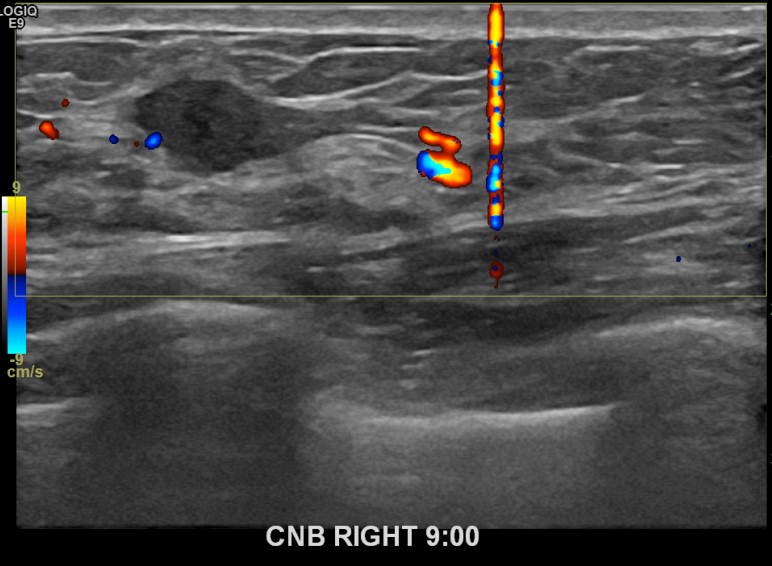

상기환자 본원에서 꾸준히 추적관찰하던 40대 여성분으로 새롭게 생겨난 혹 있어 우측유방멍울 조직검사시행후 유방암 진단되었습니다.